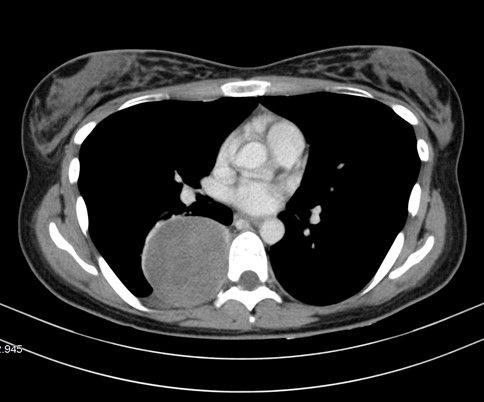

Una masa extrapulmonar sólo se puede confirmar con la radiografía cuando hay una lesión costal, cosa que no ocurre con este paciente, por lo que necesitará confirmarse la lesión con una TC. Además, la radiografía no es suficiente para localizar exactamente dónde se encuentra la lesión. Para ello, también usamos TC, con el que delimitamos mejor la lesión y nos sirve para evaluar las lesiones de la pared torácica y de la pared pleural.

La TC es una técnica disponible, económica y rápida que permite valorar el tórax con gran eficacia.